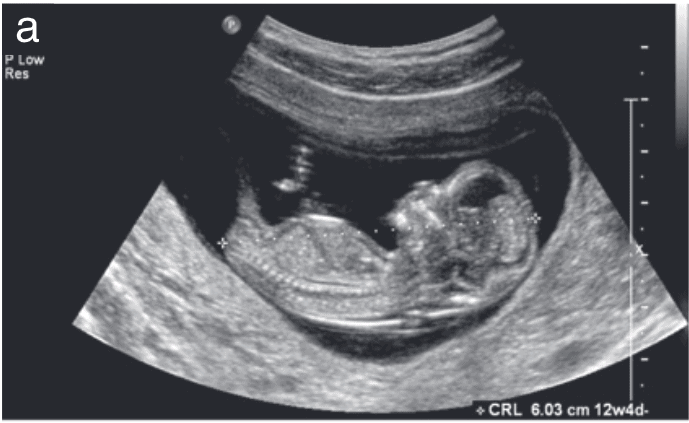

Obstetric ultrasonography, often referred to as a prenatal ultrasound, is not just a medical procedure; it is a gateway to peace of mind for expecting mothers. This non-invasive imaging technique provides a window into the womb, allowing mothers like Kavita to witness the miraculous development of their unborn child. It is this visual connection, this first glimpse of life, that turns fear into reassurance.

For Kavita, her first ultrasound was more than just a routine check-up. It was a moment of profound emotional significance. As the sonographer guided her through the process, Kavita watched in awe as the grainy black-and-white image on the screen came to life. There was her baby, tiny yet vibrant, moving within her. The rhythmic pulsing of the little heart resonated with her own, creating a bond that transcended words.

But beyond the emotional connection, obstetric ultrasonography plays a crucial role in prenatal care. It provides vital information about the baby's development, detecting any anomalies or potential complications early on. This early detection is crucial, allowing for timely medical interventions that can significantly improve outcomes for both mother and child.